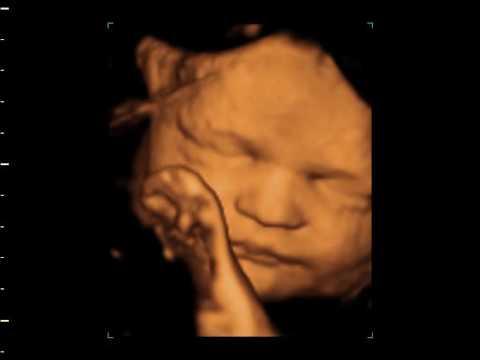

3d 4d Ultrasound Suffolk Ny

3d 4d Hd Ultrasound 3d Maternity Imaging Gender Reveal New